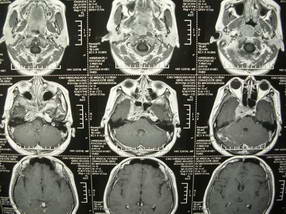

男、30、发现鼻咽部肿瘤侵犯海绵窦,未发现明显淋巴肿。请问国内那家医院治疗鼻咽部肿瘤最好?手术以何种方式为主?病灶可否全部切除?急切期待的大家的帮助。

扫描示鼻咽腔不对称,中度狭窄,右侧咽隐窝消失,局部软组织肿块,鼻咽右侧壁增厚形成肿块,突入鼻咽腔,肿块平扫呈等密度,肿块向深部侵润,右侧翼内外肌受侵,右侧咽旁间隙变窄;向后生长,头长肌界线欠清,向后上生长侵犯同侧颈动脉鞘区。双侧海绵窦增宽,内见软组织影与鼻咽部肿块相连。考虑鼻咽癌。鼻咽癌主要是放射治疗,且效果较好;到当地有治疗设备较大医院治疗即可。

这个病例有点特殊,和常见的鼻咽癌不太一样,以向颅内侵犯为主,骨质破坏区小。鼻咽癌首先要考虑,有没有其他可能?本人不会看mr片,期待有人能讲解,期待病理。